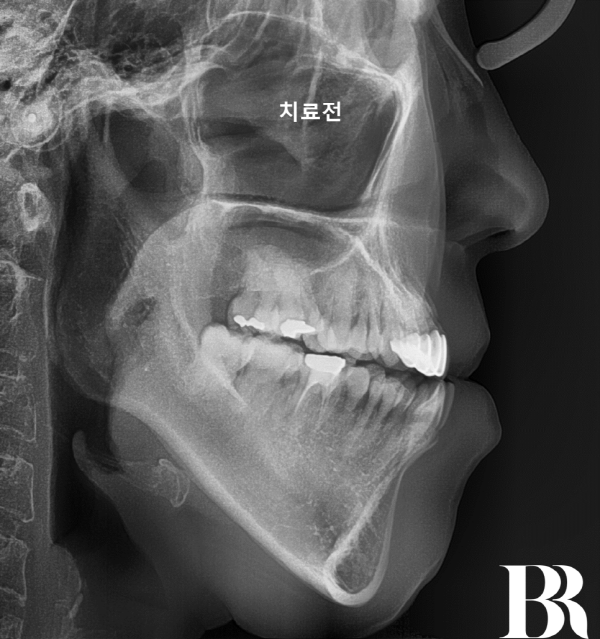

※ 치료 전 상태

-심한 반대교합(주걱턱)

-음식물을 앞니로 끊지 못함

-아래턱 돌출로 인한 심미적 스트레스

치료 전 옆모습입니다.

거꾸로 물리는 정도만 봐도

얼마나 심한 상태인지를

어렵지 않게 알 수 있습니다

수술직후 옆에서 찍은 엑스레이 : 주걱턱 이미지가 많이 개선되었다.